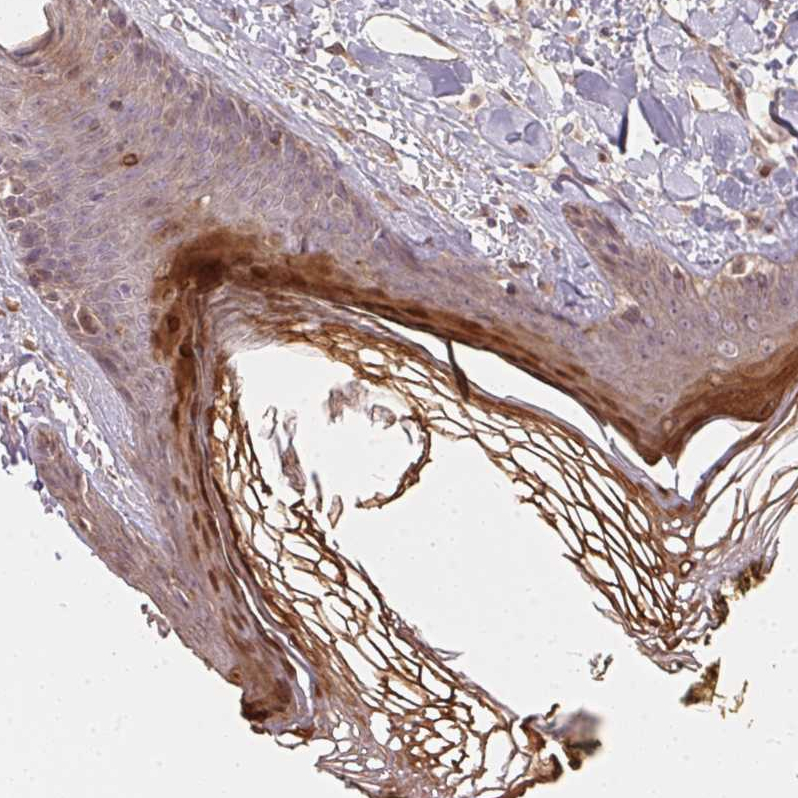

Immunohistochemistry analysis in human skin and liver tissues using HPA039548 antibody. Corresponding BLMH RNA-seq data are presented for the same tissues.